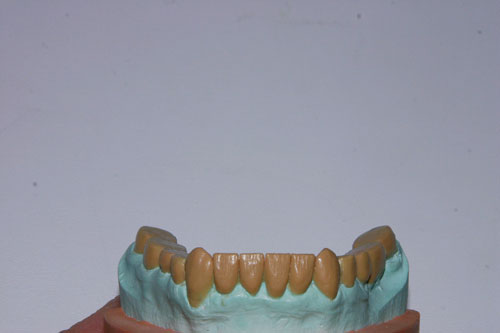

Los sectores posteriores, se construyen:

Primero el inferior acorde con la Guía Anterior antedicha, para de esta manera delinear la Espiral Dinámica ideal para el caso.

A continuación, se construye el sector de la Tabla Premolar Molar del superior.

Alineación Tridimensional Inf.